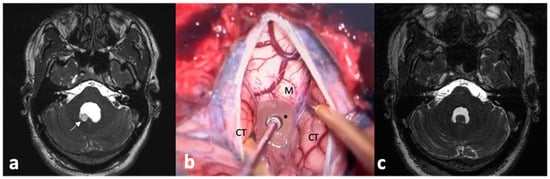

- Sharma, B.S.; Sawarkar, D.P.; Verma, S.K. Endoscopic Management of Fourth Ventricle Neurocysticercosis: Description of the New Technique in a Case Series of 5 Cases and Review of the Literature. World Neurosurg. 2019, 122, e647–e654. [Google Scholar] [CrossRef]

- Singh, S.; Marutirao, R.; Deora, H.; Das, K.K.; Bhaisora, K.S.; Sardhara, J.; Parab, A.; Mehrotra, A.; Srivastava, A.K.; Jaiswal, S.; et al. Endoscopic Route for Excision of Intraventricular Neurocysticercosis: Light At the End of the Tunnel. World Neurosurg. 2019, 125, e74–e81. [Google Scholar] [CrossRef] [PubMed]

- Husain, M.; Jha, D.K.; Rastogi, M.; Husain, N.; Gupta, R.K. Neuro-endoscopic Management of Intraventricular Neurocysticercosis (NCC). Acta Neurochir. 2007, 149, 341–346. [Google Scholar] [CrossRef]

- Torres-Corzo, J.G.; Tapia-Pérez, J.H.; Vecchia, R.R.; Chalita-Williams, J.C.; Sánchez-Aguilar, M.; Sánchez-Rodríguez, J.J. Endoscopic Management of Hydrocephalus Due to Neurocysticercosis. Clin. Neurol. Neurosurg. 2010, 112, 11–16. [Google Scholar] [CrossRef] [PubMed]

- Proaño, J.V.; Torres-Corzo, J.; Rodríguez-Della Vecchia, R.; Guizar-Sahagun, G.; Rangel-Castilla, L. Intraventricular and Subarachnoid Basal Cisterns Neurocysticercosis: A Comparative Study Between Traditional Treatment Versus Neuroendoscopic Surgery. Child’s Nerv. Syst. 2009, 25, 1467–1475. [Google Scholar] [CrossRef] [PubMed]

- Goel, R.K.; Ahmad, F.U.; Vellimana, A.K.; Suri, A.; Chandra, P.S.; Kumar, R.; Sharma, B.S.; Mahapatra, A.K. Endoscopic Management of Intraventricular Neurocysticercosis. J. Clin. Neurosci. 2008, 15, 1096–1101. [Google Scholar] [CrossRef] [PubMed]

- Zhenye, L.; Chuzhong, L.; Xuyi, Z.; Songbai, G.; Peng, Z.; Jiwei, B.; Lei, C.; Xinsheng, W. Ventriculoscopic Approach for Intraventricular Neurocysticercosis: A Single Neurosurgical Center’s Experience. World Neurosurg. 2017, 107, 853–859. [Google Scholar] [CrossRef]